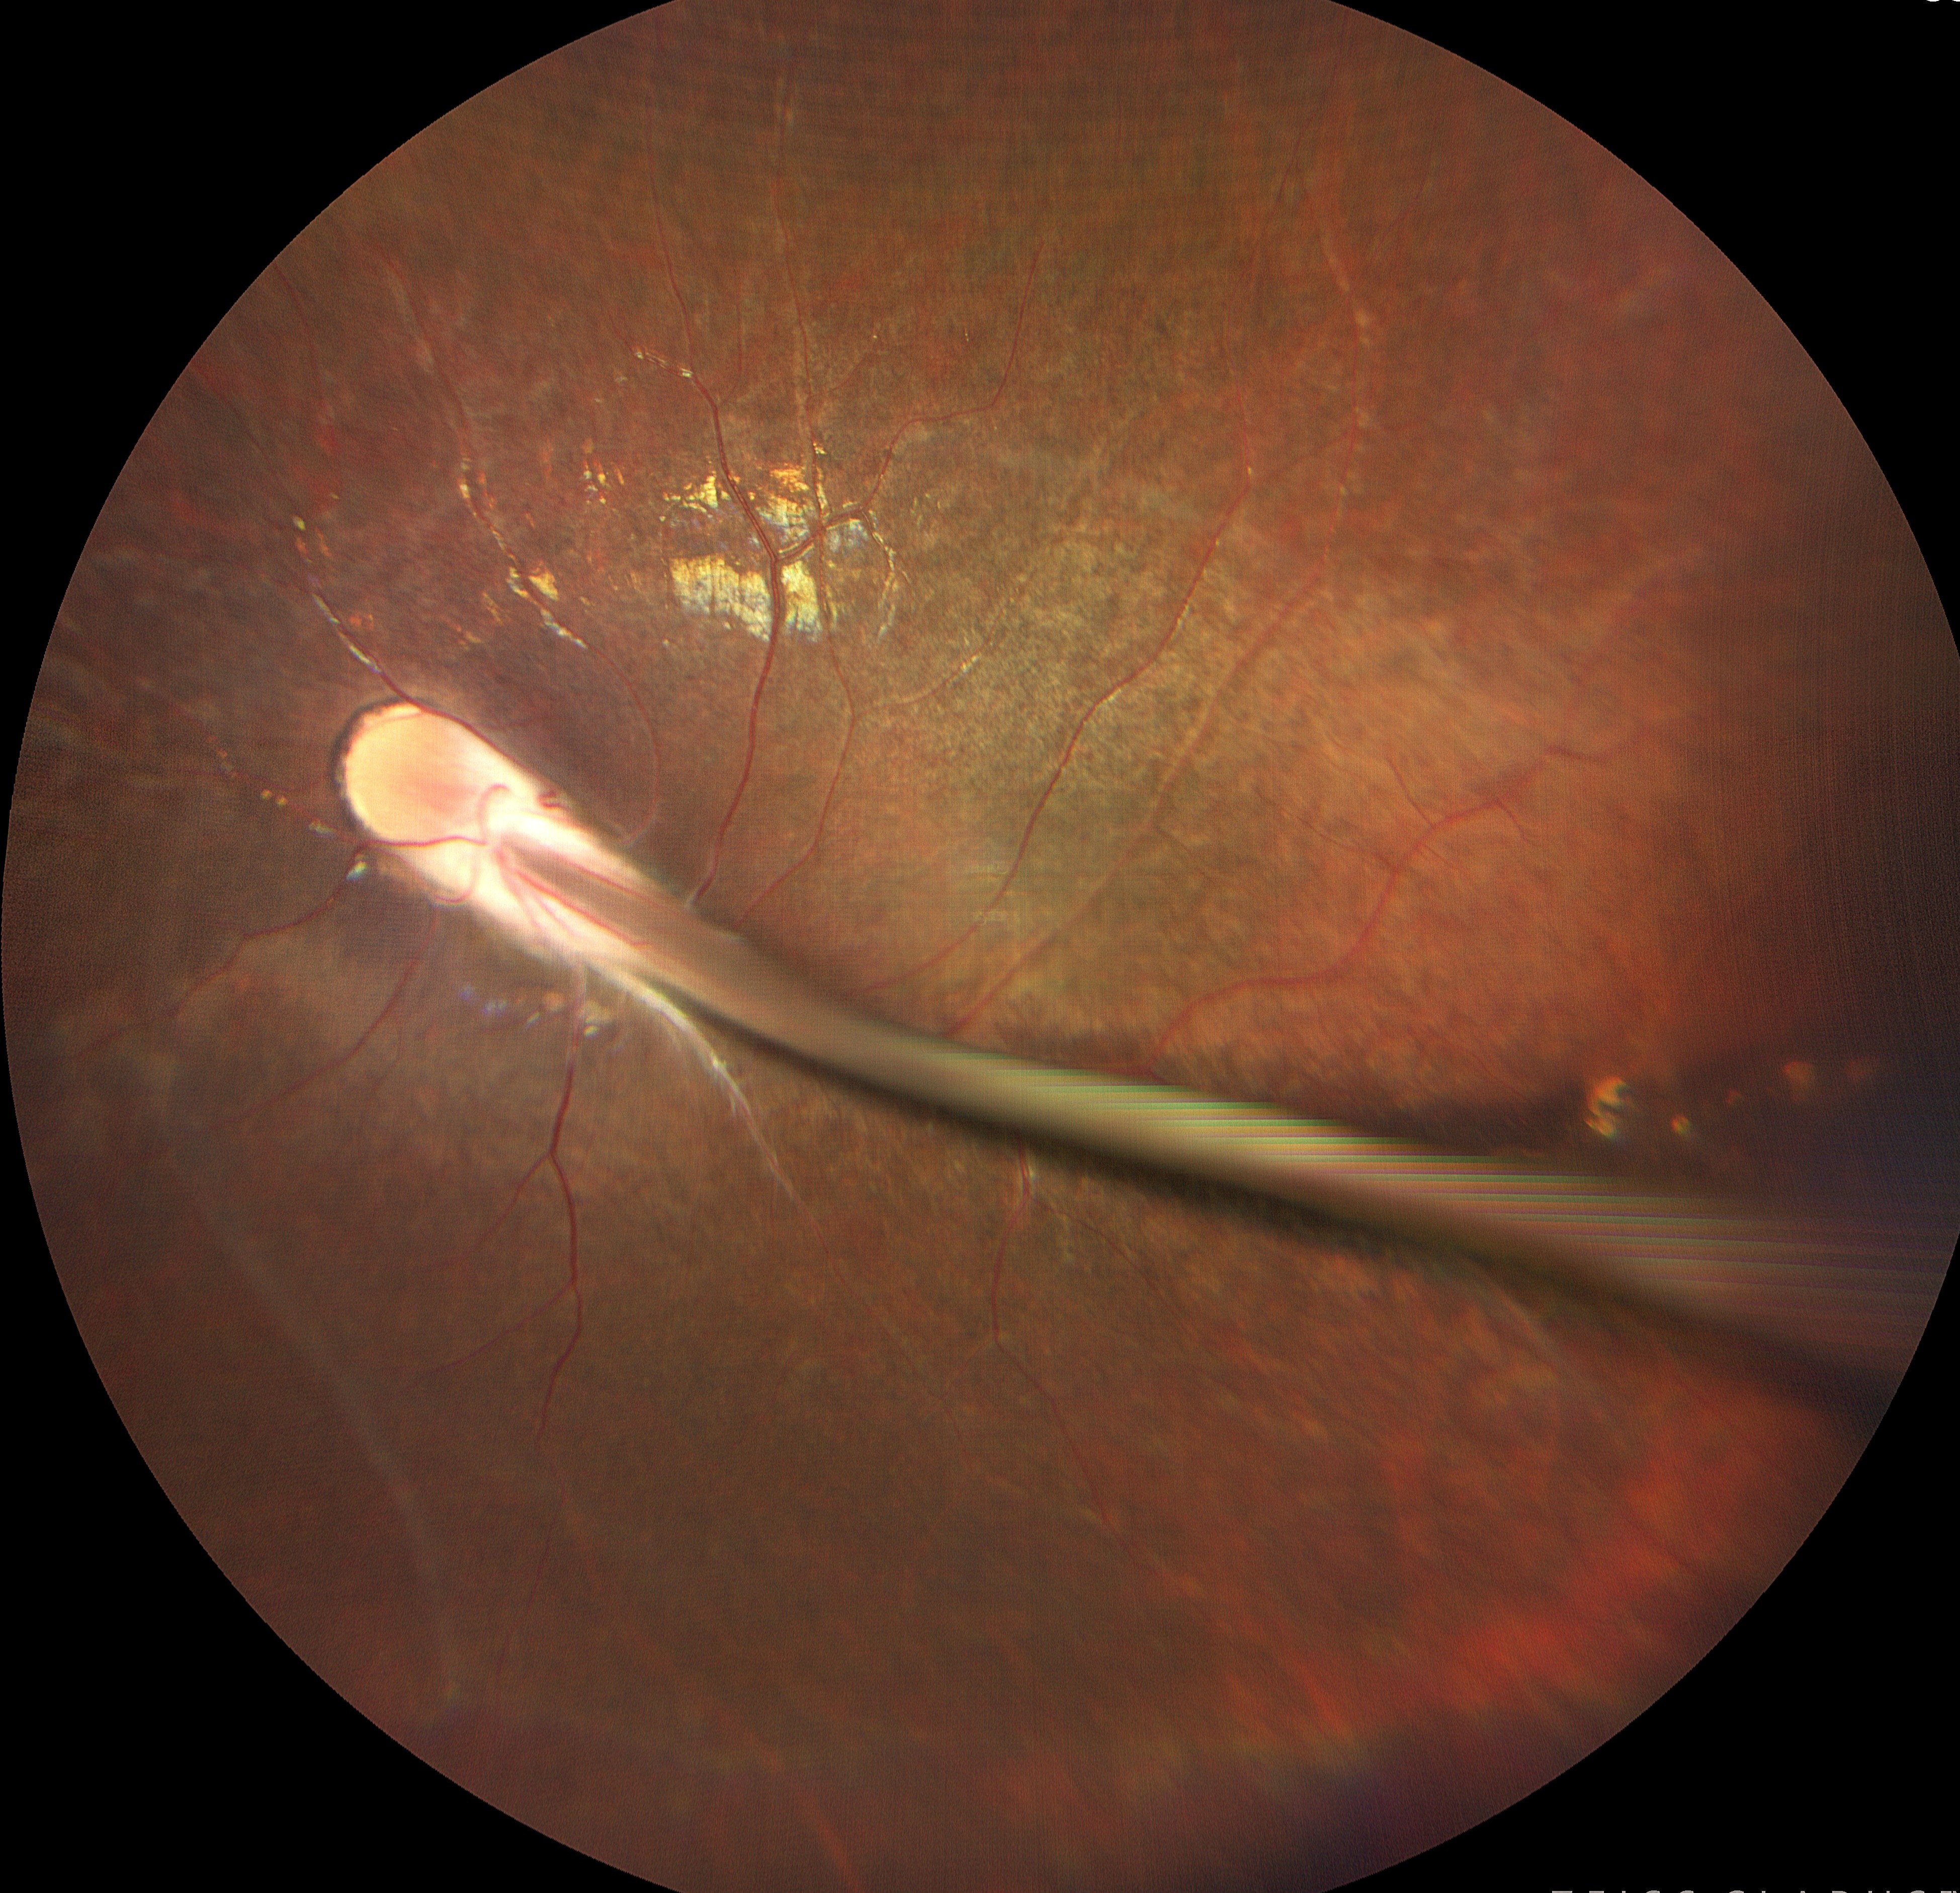

Dr. Giriraj Vibhute

Title: Frozen in time- The portrait of persistent fetal vasculature.

Description: Picture showing fundus of a 19 year old amblyopic girl. Persistent fetal vasculature/ Persistent hyperplastic primary vitreous is due to failure of regression of fetal vessels in the eye. It is the second most common cause of infantile leukocoria. These children are prone to develop amblyopia, cataract, glaucoma, retinal detachment.